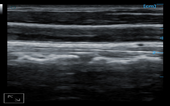

Liver + CF

Liver + CF